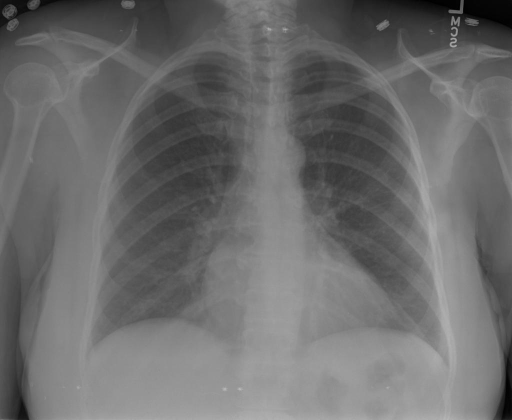

# 本文贡献 ![](./assets/images/xrayglm.png) - 借助ChatGPT以及公开的数据集,我们构造了一个`X光影像-诊断报告`对的医学多模态数据集; # 数据集 - [MIMIC-CXR](https://physionet.org/content/mimic-cxr-jpg/2.0.0/)是一个公开可用的胸部X光片数据集,包括377,110张图像和227,827个相关报告。 - [OpenI](https://openi.nlm.nih.gov/faq#collection)是一个来自印第安纳大学医院的胸部X光片数据集,包括6,459张图像和3,955个报告。 在上述工作中,报告信息都为非结构化的,不利于科学研究。为了生成合理的医学报告,我们对两个数据集进行了预处理,并最终得到了可以用于训练的**英文报告**。除此之外,为了更好的支持中文社区发展,借助ChatGPT的能力,我们将英文报告进行了中文翻译,并最终形成了可用于训练的数据集。 |数据集|数量|下载链接| |:-|:-|:-| |MIMIC-CXR-zh|-|-| |OpenI-zh|6,423|[诊疗报告](./data/Xray/openi-zh.json) 、[X光影像](https://pan.baidu.com/s/13GBsDMKf6xBZBSHpoWH_EA?pwd=k9sh)| # 快速上手 1. 安装环境 ```bash # 安装依赖 pip install -r requirements.txt # 国内换源安装依赖 pip install -i https://mirrors.aliyun.com/pypi/simple/ -r requirements.txt ``` 此时默认会安装`deepspeed`库(支持`sat`库训练),此库对于模型推理并非必要,同时部分`Windows`环境安装此库时会遇到问题。 如果想绕过`deepspeed`安装,我们可以将命令改为: ```bash # 安装依赖 pip install -i https://mirrors.aliyun.com/pypi/simple/ -r requirements_wo_ds.txt # 安装SwissArmyTransformer pip install -i https://mirrors.aliyun.com/pypi/simple/ --no-deps "SwissArmyTransformer>=0.3.6" ``` 2. 模型推理 CLI推理: ```python python cli_demo.py --from_pretrained checkpoints/finetune-XrayGLM-05-25-01-04 --prompt_zh '详细描述这张胸部X光片的诊断结果' ``` 更多[参数](https://github.com/WangRongsheng/XrayGLM/blob/main/cli_demo.py#L16) # 效果展示 诊断: |X光影像|诊疗报告(医生)|XrayGLM| |:-|:-|:-| |![](./data/Xray/2_1.png)|根据X射线图像,心脏大小正常,肺部看起来很清晰。已经排除了肺炎、积液、水肿、气胸、腺病、结节或肿块的存在。该发现表明一切正常。换句话说,总体印象是胸部正常。|X光片显示,心脏大小正常。肺部没有气胸或胸腔积液的证据。骨骼结构看起来没有任何异常。总的来说,X光片表明没有发现急性心肺疾病的迹象。| |![](./data/Xray/2882_1.png)|X光图片显示没有扭曲的区域、可疑的骨质不透明度或胸腺积液。心脏大小轻微增大,但非常稳定。此外,没有气胸的证据,肺野也正常。总体来说,X光片显示没有急性心脏异常,但要注意轻微的心脏扩大。|X光片显示,心脏大小正常。肺部和纵隔轮廓清晰,没有气胸或胸腔积液的证据。骨骼结构完整,没有任何急性异常。| |![](./data/Xray/2577_1.png)|心影形态在正常范围内。没有急性骨质异常。有可能出现没有明显的吸水或肺实质状况的线索。没有大面积积液或气胸。有可能怀疑其有误吸或肺实质问题。为了确诊和治疗,可能需要进行适当的影像学随访。|心脏大小正常,肺部和纵隔轮廓清晰。没有急性异常或活动受限的证据。没有任何明显的气胸、胸腔积液或肺不张的迹象。此外,也没有发现任何局灶性骨质异常或其他急性疾病。| 多轮对话: |X光影像|诊疗报告(医生)| |:-|:-| |![](./data/Xray/861_1.png)|右侧主动脉突出观察到。心脏大小正常。胸部未发现明显的肺气肿、胸膜积液或可疑的肺部病变。报告指出已知右侧主动脉情况正常。| ```bash >> X光影像路径:./data/Xray/861_1.png >> 用户:这是一张什么图? >> XrayGLM:这张图片显示的是一张肺部检查的X光片。 >> 用户:请描述这张胸部X光片的诊断结果 >> XrayGLM:心脏大小正常,肺部清晰。没有急性心肺疾病的证据。 >> 用户:是否存在肺气肿? >> XrayGLM:没有肺气肿。心脏大小正常,肺部清晰。没有发现急性心肺疾病的证据。 >> 用户:平时饮食该注意什么? >> XrayGLM:饮食应该健康,均衡。建议增加蛋白质的摄入量,因为蛋白质有助于维持肌肉和骨骼的健康。多食用蔬菜、水果、全谷物以及健康的脂肪来源如橄榄油、鱼类等可以帮助获得足够的维生素和矿物质。此外,避免过度饮酒或吸烟,这些习惯可能会对心脏健康产生负面影响。 ``` # 项目致谢 1. [VisualGLM-6B](https://github.com/THUDM/VisualGLM-6B)为我们提供了基础的代码参考和实现; 2. [MiniGPT-4](https://github.com/Vision-CAIR/MiniGPT-4)为我们这个项目提供了研发思路; 3. ChatGPT生成了高质量的中文版X光检查报告以支持XrayGLM训练; 4. [gpt_academic](https://github.com/binary-husky/gpt_academic)为文档翻译提供了多线程加速; 5. [MedCLIP](https://github.com/RyanWangZf/MedCLIP) 、[BLIP2](https://huggingface.co/docs/transformers/main/model_doc/blip-2) 、[XrayGPT](https://github.com/mbzuai-oryx/XrayGPT) 等工作也有重大的参考意义; ![](./assets/images/mpu.png) 这项工作由[澳门理工大学应用科学学院](https://www.mpu.edu.mo/esca/zh/index.php)硕士生[王荣胜](https://github.com/WangRongsheng) 、[段耀菲](https://github.com/IsBaSO4) 、[李俊蓉](https://github.com/lijunrong0815)完成,同时这项工作受到[檀韬](https://scholar.google.com/citations?hl=zh-CN&user=lLg3WRkAAAAJ)副教授、[彭祥佑](http://www.patrickpang.net/)老师的帮助支持。 *特别鸣谢:[USTC-PhD Yongle Luo](https://github.com/kaixindelele) 提供了有3000美金的OpenAI账号,帮助我们完成大量的X光报告翻译工作 # 免责声明 本项目相关资源仅供学术研究之用,严禁用于商业用途。使用涉及第三方代码的部分时,请严格遵循相应的开源协议。模型生成的内容受模型计算、随机性和量化精度损失等因素影响,本项目无法对其准确性作出保证。即使本项目模型输出符合医学事实,也不能被用作实际医学诊断的依据。对于模型输出的任何内容,本项目不承担任何法律责任,亦不对因使用相关资源和输出结果而可能产生的任何损失承担责任。 # 项目引用 如果你使用了本项目的模型,数据或者代码,请声明引用: ```bash @misc{wang2023XrayGLM, title={XrayGLM: The first Chinese Medical Multimodal Model that Chest Radiographs Summarization}, author={Rongsheng Wang, Yaofei Duan, Junrong Li, Patrick Pang and Tao Tan}, year={2023}, publisher = {GitHub}, journal = {GitHub repository}, howpublished = {\url{https://github.com/WangRongsheng/XrayGLM}}, } ``` # 使用许可 此存储库遵循[CC BY-NC-SA](https://creativecommons.org/licenses/by-nc-sa/4.0/) ,请参阅许可条款。